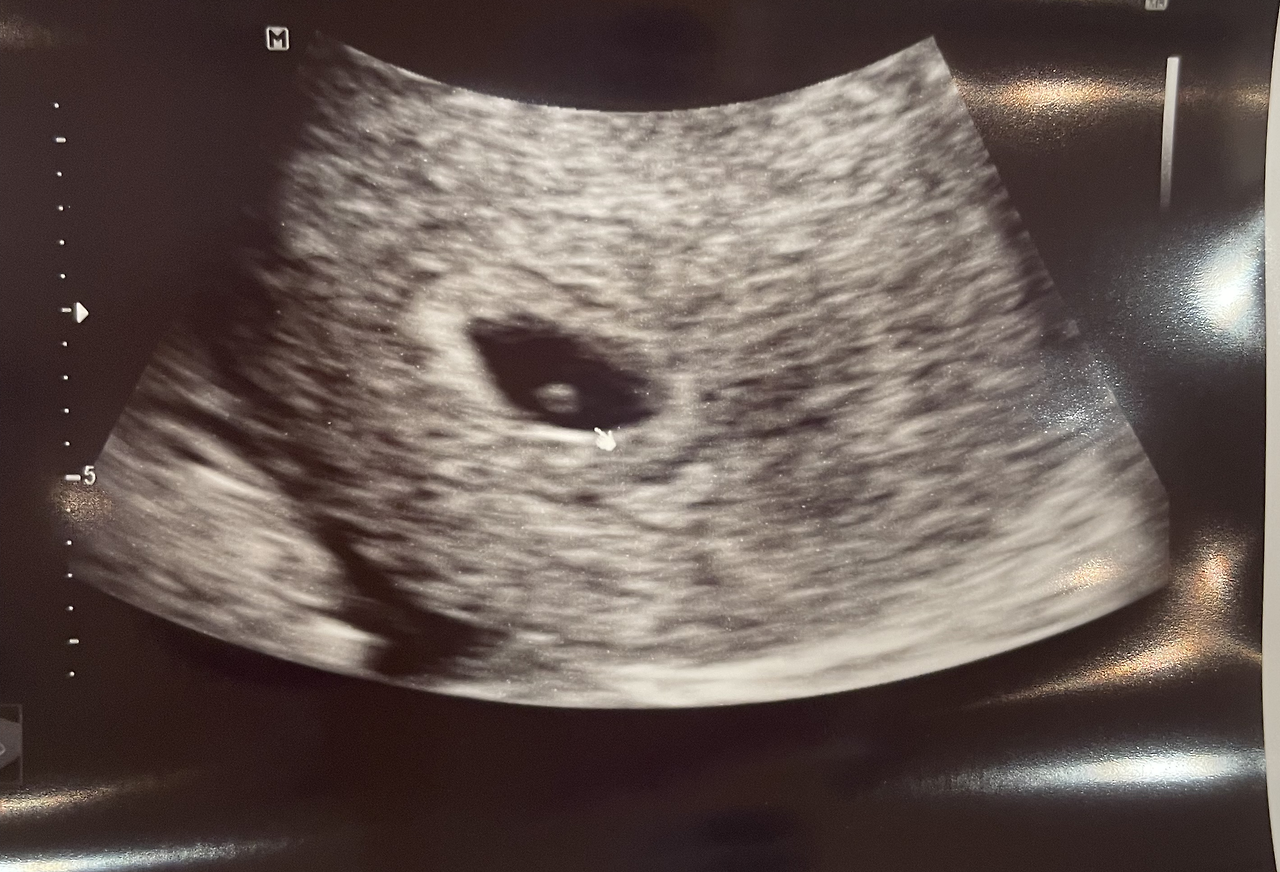

아기집과 난황

"오늘은 아기집이 보이네요."

질초음파로 내 자궁 속을 확인하자마자 내 눈에도 아기집이 보였다. 초점을 잘 맞추니 난황까지 보였다. 아기집의 크기를 재어 확인한 주수는 5주 2일.

아직 아기는 안 보이는 시기로, 2주 뒤에 다시 내원하면 아기를 초음파로 확인할 수 있고, 심장소리를 들을 수 있다고 한다.